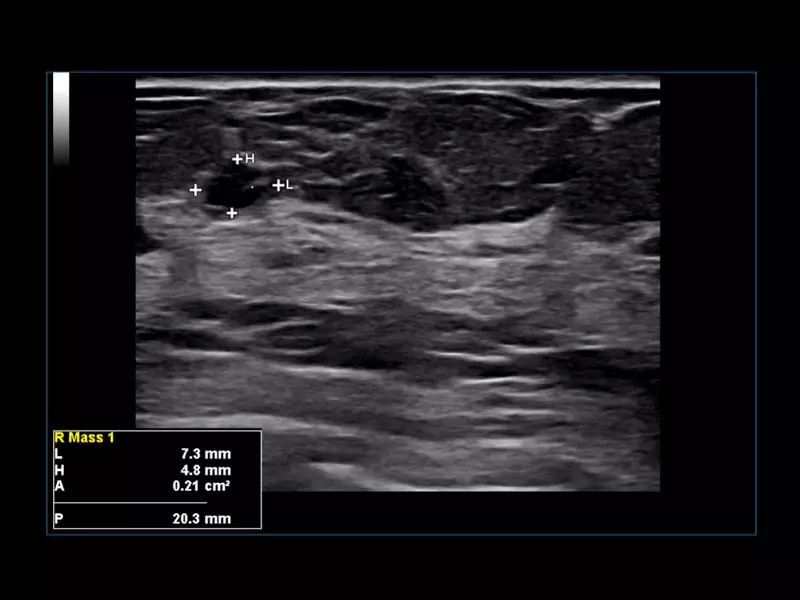

Q7 - GI Small parts

Q7 - GI Small parts